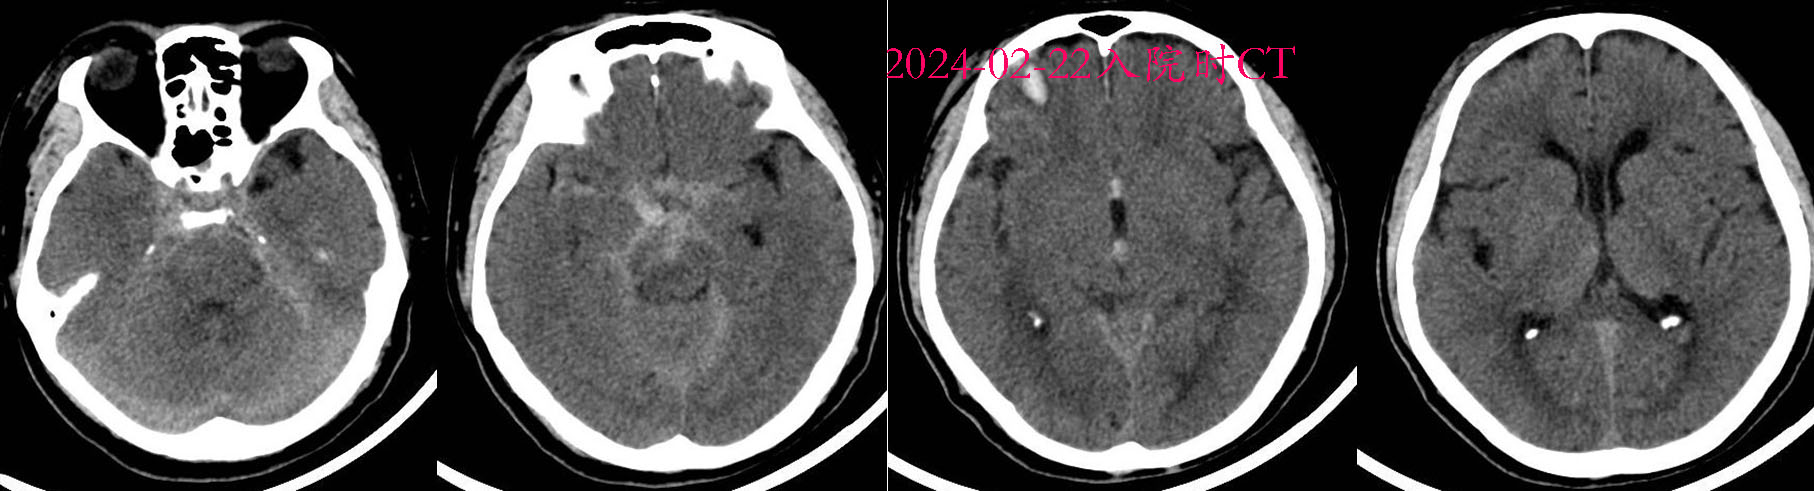

入院时CT。

入院后脑脊液耳漏,行DSA排除动脉瘤。先后给予美罗培南抗感染治疗,行气管切开,患者反复发热,脑脊液耳漏自行停止。留取脑脊液培养见革兰阴性杆菌生长,予万古霉素联合美罗培南抗感染治疗,继续行腰椎穿刺术释放脓性脑脊液。